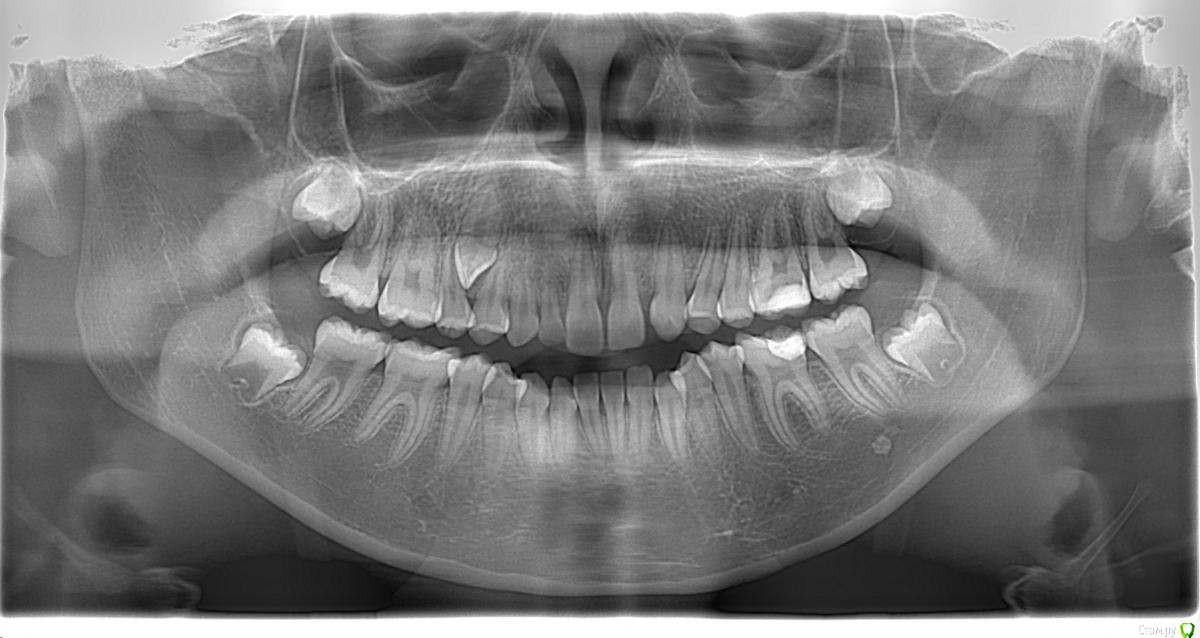

Opdihatop Опубликовано 20 февраля, 2017 Автор Поделиться Опубликовано 20 февраля, 2017 52, 53 молочные. 12, 22 - адентия. Клык пойдет на место 13. Когда-то на курсе Рафаэля Спены видел подобное, но, к сожалению не зафиксировал на фото. В общем и целом принцип помню. Но тут есть одно огромное НО... 14, 15 началась резорбция верхушек из-за 13 зуба, что видно по КТ. Ссылка на комментарий

Opdihatop Опубликовано 20 февраля, 2017 Автор Поделиться Опубликовано 20 февраля, 2017 (изменено) вот такая штучка еще в кости... Видел, на вид - простая остеомка, так что пугать пациента не буду, передвижению зубов не мешает. а про каких именно классиков Вы говорите? (это я для себя, для развития..) Вот простите, не вспомню, читал монографию какого-то итальянца еще на этапе обучения, так там было сказано вообще их удалять, особенно при транспозиции через ц.л. у ВАшей девочки я бы удаляла восьмерки, ставила винты в подскуловую область , часть зубов назад, а часть - пружинами вперед. создавая место. про клык - здесь конечно по КТ надо смотреть, куда его тащить и как открывать. Возможно лучше вначале открыть место (раздвинуть 5ку и 4ку) а потом клык поставить между ними. Клык станет 4кой а 4ка клыком. (имхо) Подскуловые импланты, это классно, только вот в Украине этих корейцев не продают пока (Диаметра не хватает и длины). Дистализирую пружинами при непрямом анкораже на микроимплантате между 5 и 6. Как я собирался тянуть клык вперед? На 14, 15 ставятся брекеты от нижних премоляров и ставятся они на толстую композитную подушку, которая постепенно утолщается. Таким образом зубы постепенно уходят орально, а их корням придается небный торк, освобождая путь в кости для 13. Затем при помощи компактостеотомии быстро мезиализируется 13, затем 14 и 15 плавно перемещаются назад (хотя 15 это вряд ли коснется... его я планирую перед этим дистализировать). Сам я такое не делал, но видел на курсе. Вот, выпал шанс попробовать. Зачем? Во-первых, научный интерес, во-вторых, родители категорически против ремоделирования коронок зубов... Изменено 20 февраля, 2017 пользователем Opdihatop Ссылка на комментарий